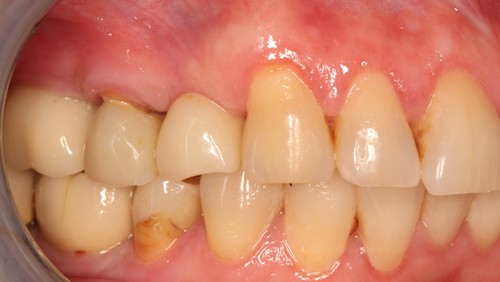

До

После